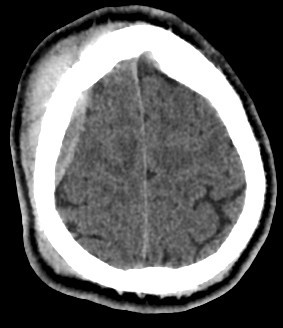

• Subdural hematoma: Crescentic shape, crosses sutures, follows the contour of the brain.

• Hemorrhagic contusion: Intra-axial and irregular.

• Epidural abscess: Similar location but rim-enhancing on post-contrast scan.